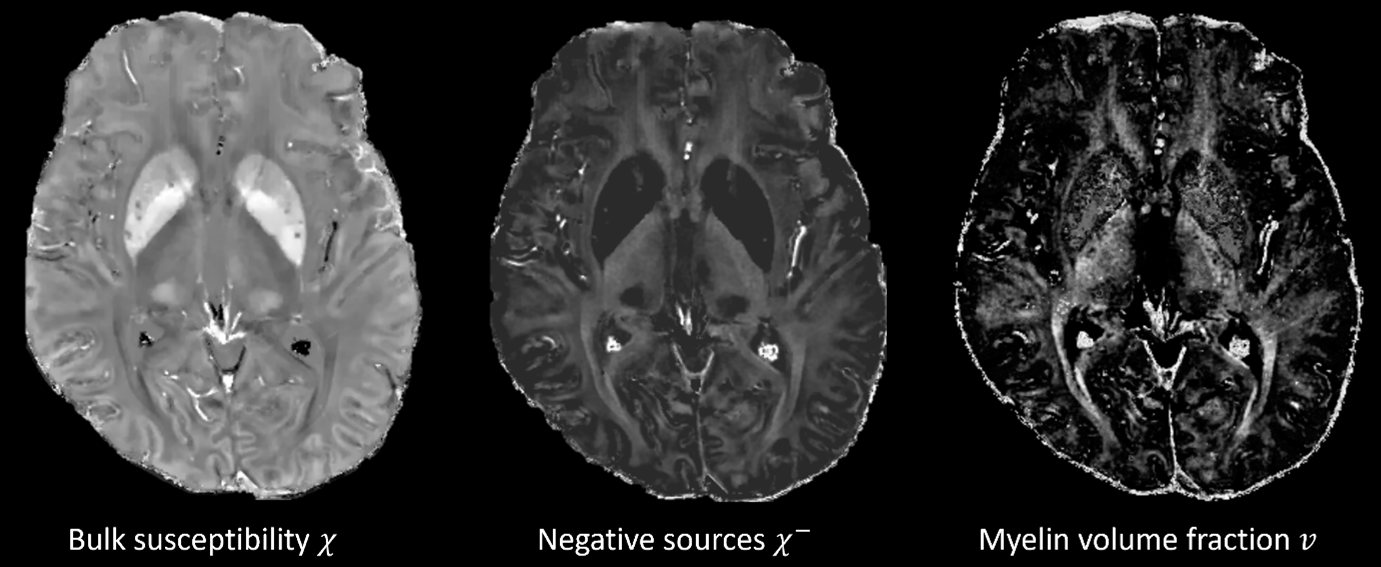

Results: The proposed atlas shows improvement over the McGill atlas in segmentations [figure2]. Applying transforms to relaxation and susceptibility map generates atlases in [fgure3]. The DN visualization, STN/SN delineation and GP/PUT contrast is improved in the susceptibility maps χ, χ+ [figure4] compared to structural T1w. White matter tracts on negative source χ– and myelin fraction v are visible [figure5].

Conclusion: The proposed tool creates high contrast atlases of DBS targets and myelin mapping improves depiction of white matter tracts, critical trajectory planning. The added contrasts are reconstructed the presurgical QSM sequence. Other targets including ventral intermediate, centromedian, and the anterior thalamic nuclei can be explored. Output segmentations aid in surgical outcome prediction29,30 from preoperative imaging.

White matter tracts on mGRE maps.

Improved visualization GP, PUT, STN, SN, and DN.